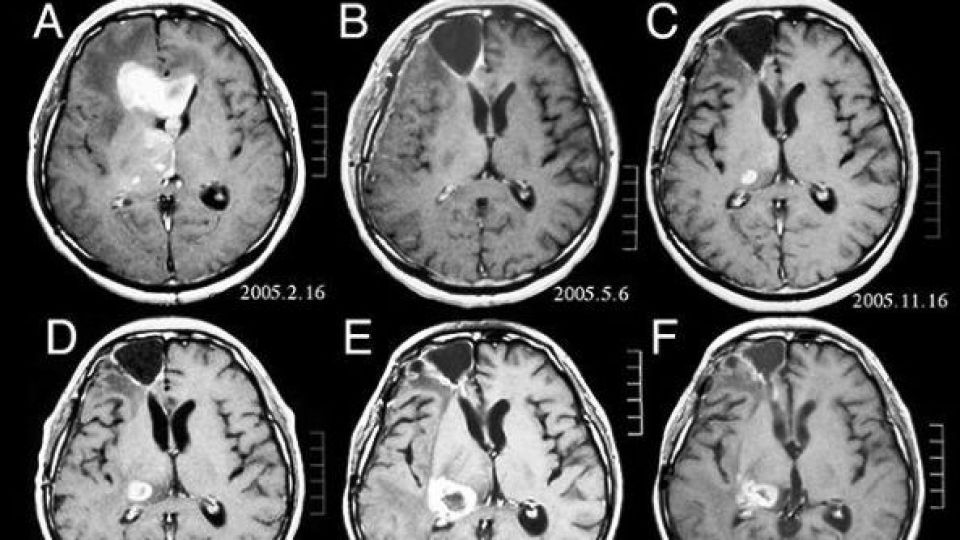

لوسمی (سرطان خون) و تومورهای مغزی از شایع ترین بدخیمی های ناشی از رادیواکتیویته در بین کودکان و افراد جوان هستند. از اینرو محققان به ارزیابی ریسک تومور مغزی و لوسمی در کودکان بعد از قرارگیری در معرض اشعه ناشی از سی تی اسکن پرداختند.

نتایج نشان داد بروز سرطان ۱.۵ برابر بیش از حدانتظار است. خطر نسبی در مورد ابتلا به تمام انواع تومورهای مغزی برای بالاترین میزان دوز اشعه بکارگرفته شده بین ۲ تا ۴ برابر افزایش یافته بود.